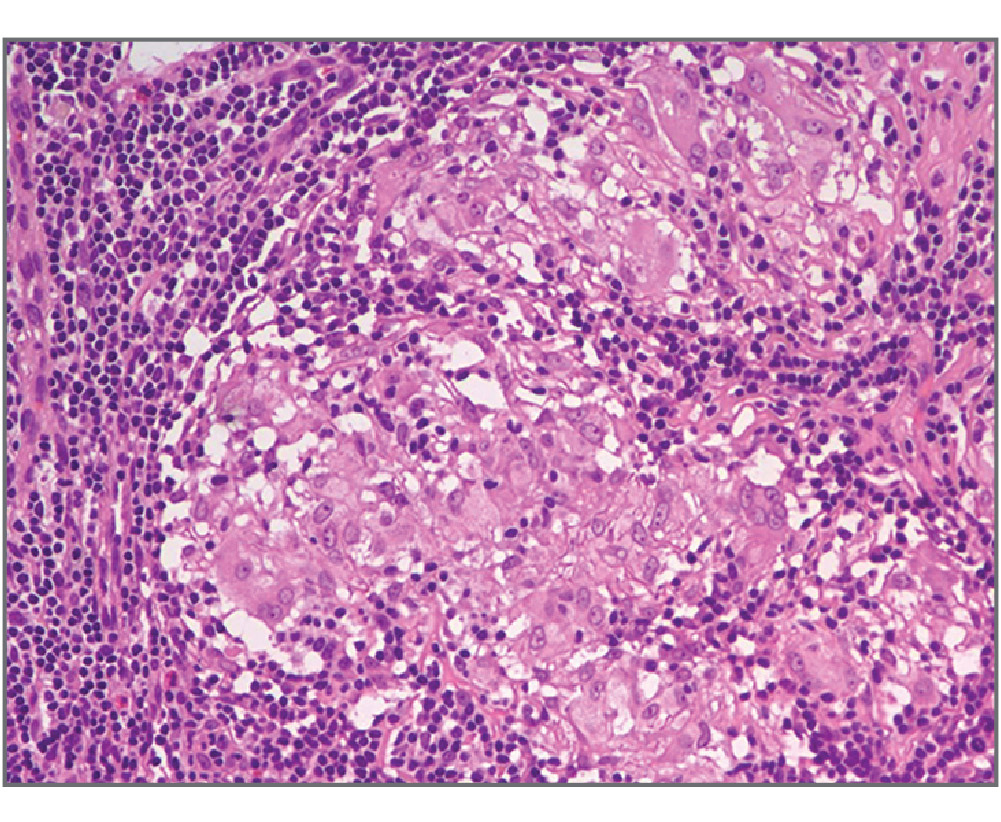

С декабря 2017 г. пациентка начала отмечать периодическое повышение температуры тела до 38ºС, появление болей в крупных и мелких суставах, сухого кашля, одышки при физической нагрузке, болезненных красноватых участков уплотнения на коже обеих голеней. При флюорографии выявлено увеличение внутригрудных лимфатических узлов (ВГЛУ), подтвержденное данными компьютерной томографии органов грудной клетки. С целью морфологической верификации патологического процесса в феврале 2018 г. выполнена видеоассоциированная торакоскопическая биопсия ВГЛУ; по данным гистологического заключения в ткани лимфоузла обнаружены множественные эпителиоидно-клеточные гранулемы без признаков казеозного некроза (рис. 1). Установлен диагноз саркоидоза с поражением ВГЛУ; в конце февраля 2018 г. начата терапия глюкокортикостероидами – преднизолоном в дозировке 35 мг/сут, с выраженным положительным эффектом в виде полного регресса указанных симптомов. С мая 2018 г. начато постепенное снижение дозировки преднизолона до полной отмены в сентябре того же года.

Рис. 1. ВГЛУ. Лимфоидная ткань вытеснена дискретными эпителиоидно-клеточными гранулемами без казеозного некроза. Окраска гематоксилин-эозином; ×200.